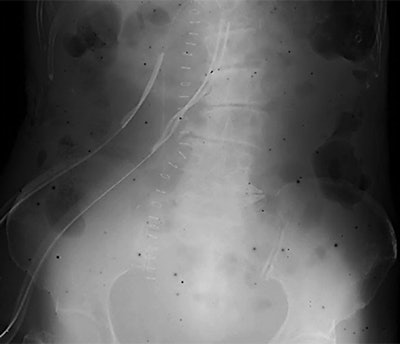

Mobile x-ray image of an 80-year-old-woman with ileus, obtained on March 18, 2011, showing dark spots. All images courtesy of AJR.Worst nuclear disaster since Chernobyl

Radiologists at a Japanese hospital were baffled when dark spots began appearing on computed radiography (CR) images in March 2011. They discovered that the spots were caused by fallout from the nuclear disaster at the nearby Fukushima Daiichi nuclear power plant, according to an article in the American Journal of Roentgenology.

Researchers believe the spots represent radioisotopes from the Fukushima Daiichi accident that were suspended in the air as particulate matter. The radioisotopes filtered into CR imaging plates (IPs) to create artifacts on images. Even today, black spots are still appearing on some images, according to the team led by Yasuhiro Kashimura.

The accident spewed radioactive material into the skies and ocean waters around Japan and around the world. As nuclear experts struggled to deal with the disaster, radiology personnel at Iwaki Kyoritsu began noticing black spots on CR images -- a phenomenon also experienced at several other hospitals in Japan.